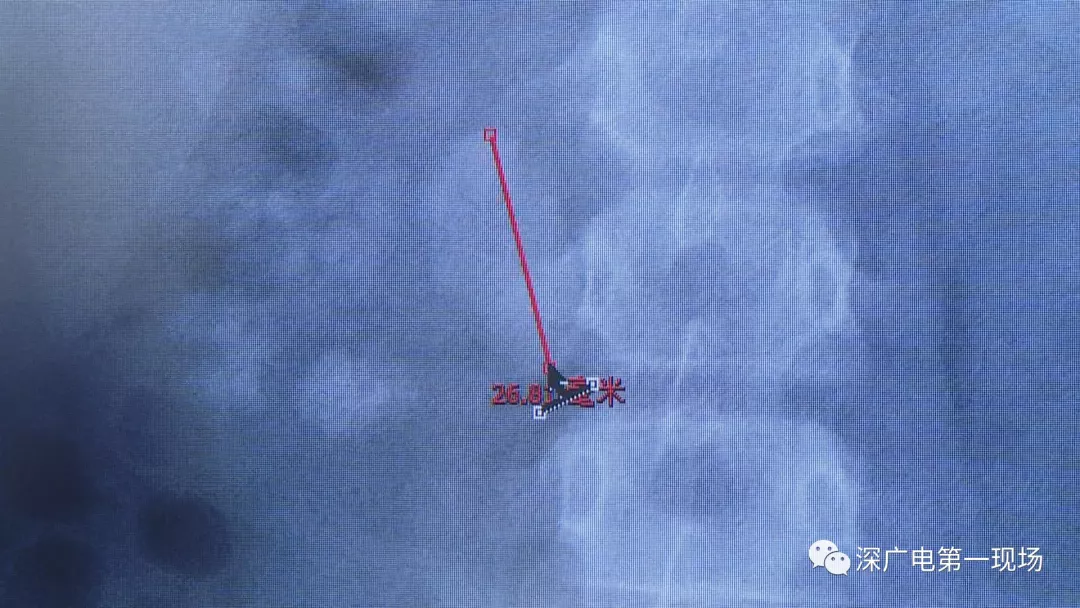

在X光圖像下,醫(yī)生發(fā)現(xiàn)小軒的雙側腎臟都內藏乾坤,密密麻麻的分布著大小不等的結石。

小軒這種情況,其中,最大的結石長約2.7厘米,寬約1.7厘米,體積堪比鵪鶉蛋,不但造成了尿路堵塞,還導致了右腎中度積水。